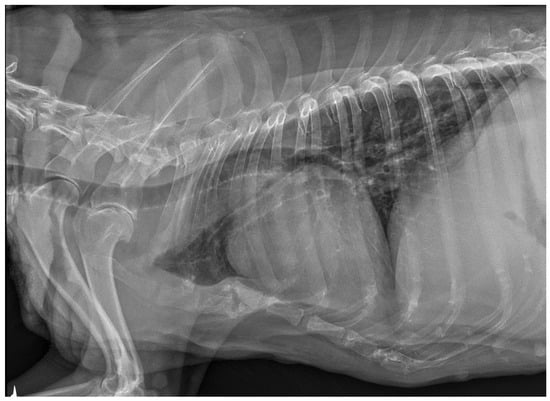

3.3. X-ray and Ultrasound Examination

No pathological changes were detected in the lung parenchyma image in the X-ray (Figure 1 and Figure 2). The ultrasound examination revealed in all views a normal, aerated lung pattern. The pleural line was intact, and A-line artifacts were present (Figure 3). The sliding sign was also observed. Echocardiography revealed a mild thickening of the mitral valve leaflets and a slight regurgitation (Figure 4) of this valve. The size of the heart chambers was within the normal range, and myocardial contractility was normal.

Figure 1.

The thoracic X-ray image in the lateral right–left (RL) position shows no pathological alterations within the lung parenchyma and cardiac silhouette. Slight elevation of the trachea in the precordial area is visible.